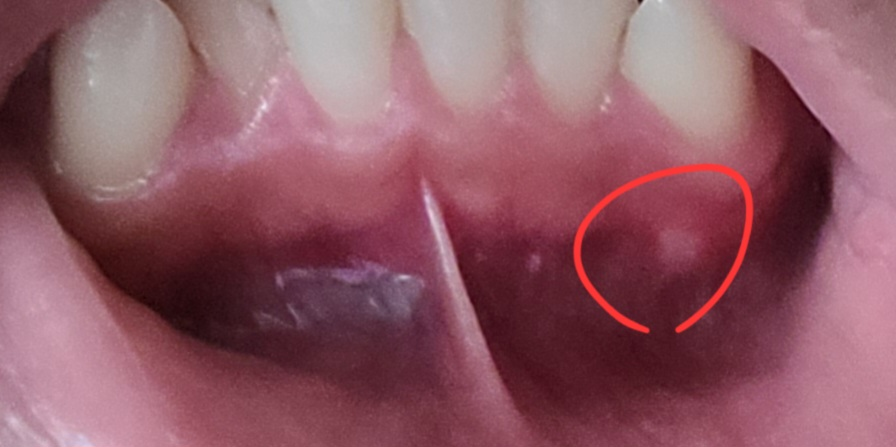

구내염 생긴거 같은데 잇몸을 누르면 아파요. 그래도 둬도 괜찮을까요?

구내염처럼 하얀 수포라고 해야하나, 그렇게 생겼어요. 구내염 부위의 잇몸을 눌러보면 아파서 그런데 병원 안가도 괜찮을까요?.

구내염이 아니고 잇몸농양일 가능성도 있어 보입니다. 사진 해상도가 좋지 않아서, 일단 치과에 가서 검사 받는 것을 추천합니다.

구내염일수도 잇지만 사진으로 보면 염증이 생겨서 그럴수도 잇으니 일단 치과에 가셔서 검진후 잇몸치료를 받아보시는게 좋을것같습니다.